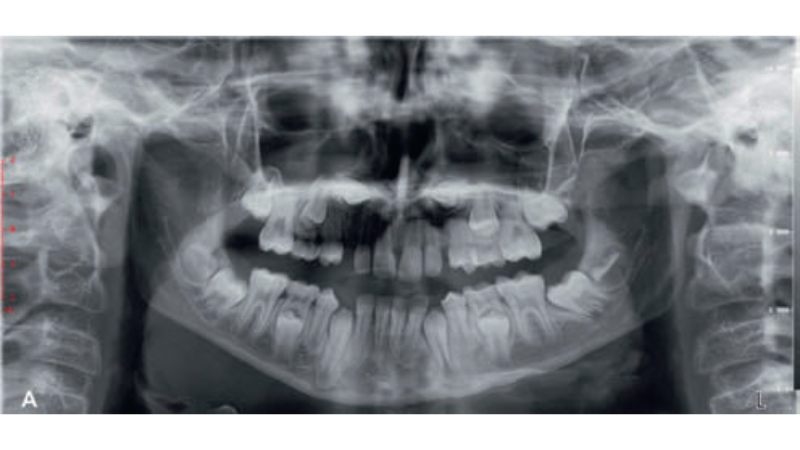

Streszczenie: Wprowadzenie: Autotransplantacja zębów to zastąpienie brakującego zęba innym zębem w obrębie uzębienia pacjenta. Zazwyczaj wiąże się to z przeniesieniem zęba zatrzymanego lub wyrzniętego z miejsca dawczego do miejsca ekstrakcji lub chirurgicznie utworzonego miejsca biorczego. Materiał i metoda: Pacjentka (12 lat) z dwoma zatrzymanymi kłami górnymi (13 i 23) została skierowana do Oddziału Ortodoncji Kliniki Stomatologii i Szpitala Uniwersyteckiego. Przeszła leczenie ortodontyczne połączone z autotransplantacją zębów 13 i 23. Opis przypadku przedstawia autotransplantację zatrzymanych kłów z nie w pełni uformowanym korzeniem i zachowaną żywotnością po zabiegu. Wnioski: Autotransplantacja obu zatrzymanych kłów pozwoliła na uzyskanie pełnej estetyki i funkcji uzębienia przy niższych kosztach. Jest to alternatywna opcja leczenia, szczególnie w przypadku zębów zatrzymanych w niekorzystnym położeniu, które uniemożliwia aktywną ekstruzję ortodontyczną, [...]